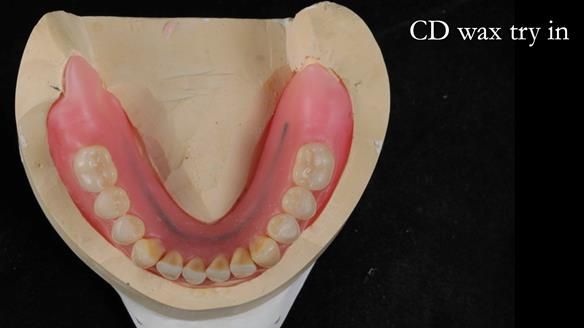

Welcome to Newsletter 62. In this edition, I walk through the process of removing 5 upper anterior teeth, adding to an existing upper RPD, followed by creating and fitting metal based complete dentures for Rafique, a 71 year old man.

The detailed clinical situation and treatment process are outlined below, with clinical work provided by me and technical work by Rowan Garstang. The treatment spanned 12 months, involving removing 5 upper anterior teeth, adding to an existing upper RPD, followed by creating and fitting metal based complete dentures.